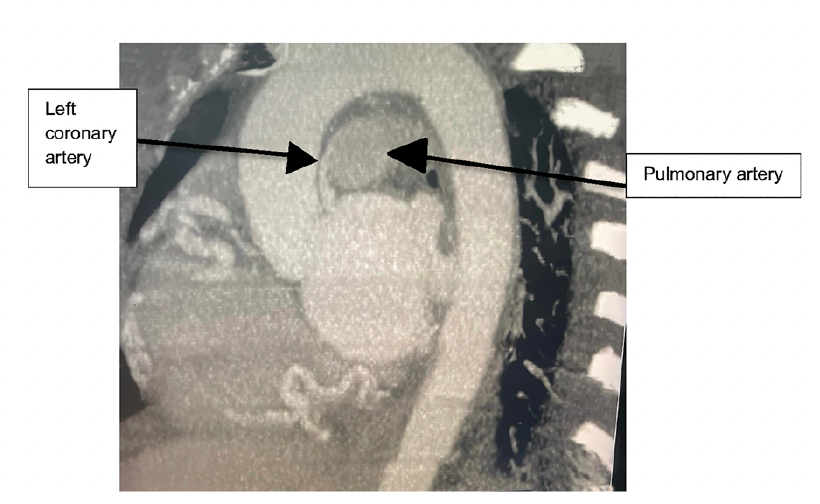

She underwent coronary angiography to assess for cardiac ischemia. Coronary angiography showed an anomalous left main coronary artery originating from the pulmonary artery, and supplying the left circumflex artery and left anterior descending artery. Angiography also demonstrated a very dilated right coronary artery supplying collaterals to the entire left coronary system and showing the left coronary artery emptying into the pulmonary artery (Figures 1-2, Video).

Video (below). Cine showing the right coronary artery with right-left collaterals filling the left coronary artery and pulmonary artery.